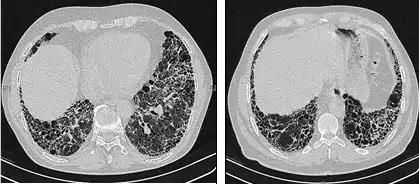

The radiological evaluation through HRCT is an essential point in the diagnostic pathway in IPF. HRCT is performed using a conventional computed axial tomographic scanner without injection of contrast agents. Evaluation slices are very thin, 1–2 mm.

Typical HRCT of the chest of IPF demonstrates fibrotic changes in both lungs, with a predilection for the bases and the periphery. According to the joint ATS/ERS/JRS/ALAT 2011 guidelines, HRCT is an essential component of the diagnostic pathway in IPF which can identify UIP by the presence of:[3]

- Reticular opacities, often associated with traction bronchiectasis

- Honeycombing manifested as cluster cystic airspaces, typically of comparable diameters (3–10 mm) but occasionally large. Usually sub-pleural and characterized by well-defined walls and disposed in at least two lines. Generally one line of cysts is not sufficient to define honeycombing

- Ground-glass opacities are common but less extensive than the reticulation

- Distribution characteristically basal and peripheral though often patchy.